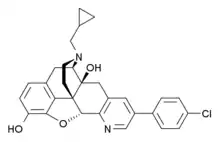

- 4-Chlorophenylpyridomorphinan

4-chlorophenylpyridomorphinan 4-chlorophenylpyridomorphinan |